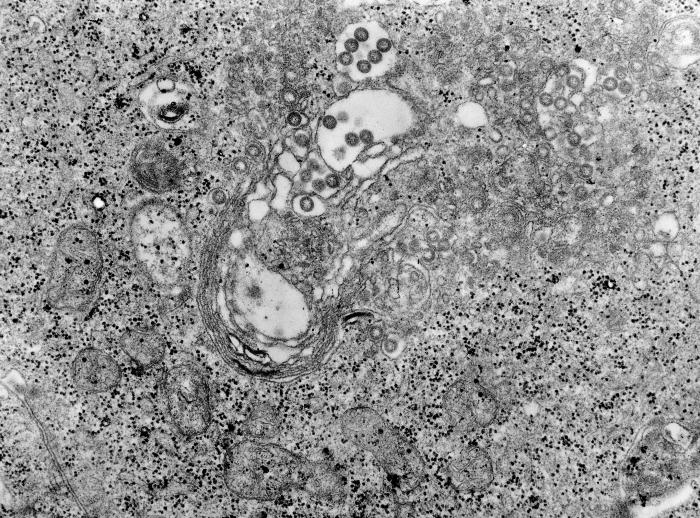

GMU Assistant Professor Dr. Kylene Kehn-Hall and others at George Mason University’s Center for Biodefense and Infectious Diseases were in the news yesterday, discussing their cutting-edge research on NanoTrap particles. The NanoTrap particles are capable of capturing and inactivating the virus in question, even when working with very low titers.  Use of the NanoParticles with Rift Valley Fever virus (RVFV), which is considered a potential bioterrorist agent, resulted in a 100-fold increase in sensitivity.

Excerpt of the study’s conclusion (published in PLOS): “This study demonstrates NanoTrap particles are capable of capturing, enriching, and protecting RVFV virions. Furthermore, the use of NanoTrap particles can be extended to a variety of viruses, including VEEV and HIV.”

(image credit: CDC/USG)